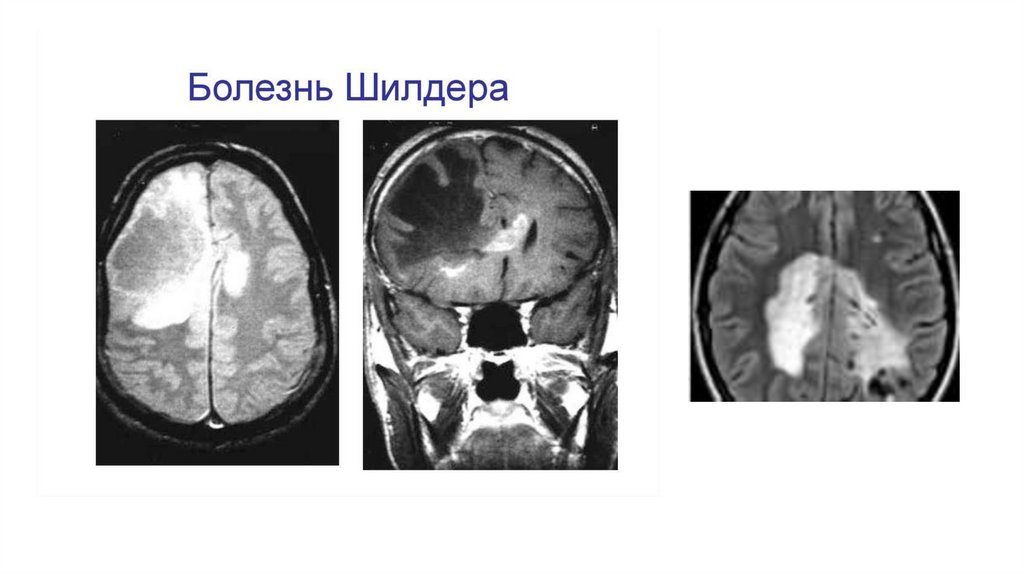

Диффузный склероз Шильдера

- очень редкое заболевание, часто рассматривается как фулминантная форма

рассеянного склероза с неуклонно прогрессирующим течением. Чаще

встречается в детском возрасте. Патоморфологическую основу составляет

диффузная демиелинизация с грубым аксональным повреждением, очагами

некроза с образованием полостей. На МРТ характеризуется обширными

относительно симметричными очагами в белом веществе полушарий с

обязательным вовлечением семиовальных центров. Поражение ствола не

характерно. Очаги увеличиваются в размерах по мере прогрессирования

заболевания, склонны к слиянию, и, захватывая большую часть полушария,

могут давать масс-эффект. Характерно накопление контрастного препарата

очагами в виде разомкнутого кольца. Очаги в гемисферах могут соединяться

через мозолистое тело. После терапии кортикостероидами очаги

демонстрируют значительное уменьшение в размерах.